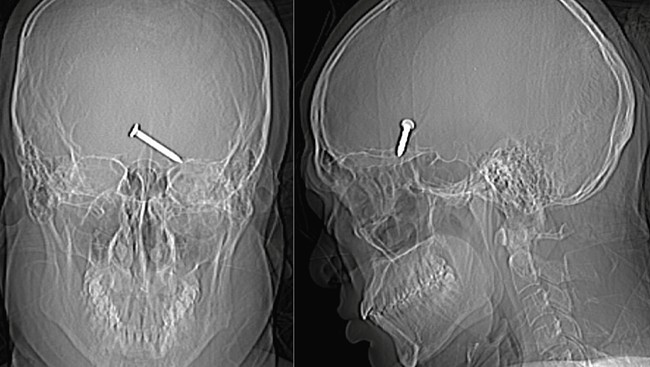

Paku menembus mata (Foto: Jurnal Cureus)

Hasil rontgen tengkorak kepala pria tersebut menunjukkan bahwa paku tersebut telah menembus lobus frontal otaknya, menyebabkan rongga matanya retak, dan ada bukti perdarahan yang meluas ke area otak di sekitarnya.

Paku tembus ke otak Foto: Cureus Journal